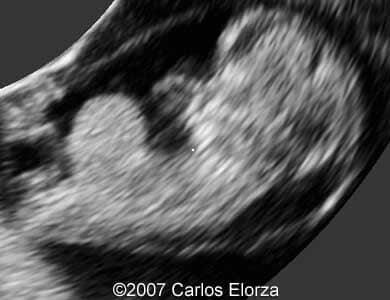

38-year-old woman (G3, P2)Ā presented in our department at 10th week of pregnancy. Ultrasound examination discovered striking nuchal edema and omphalocele with liver"s exenteration. A chorionic biopsy revealed trisomy 13. Here are someĀ images that we obtained.